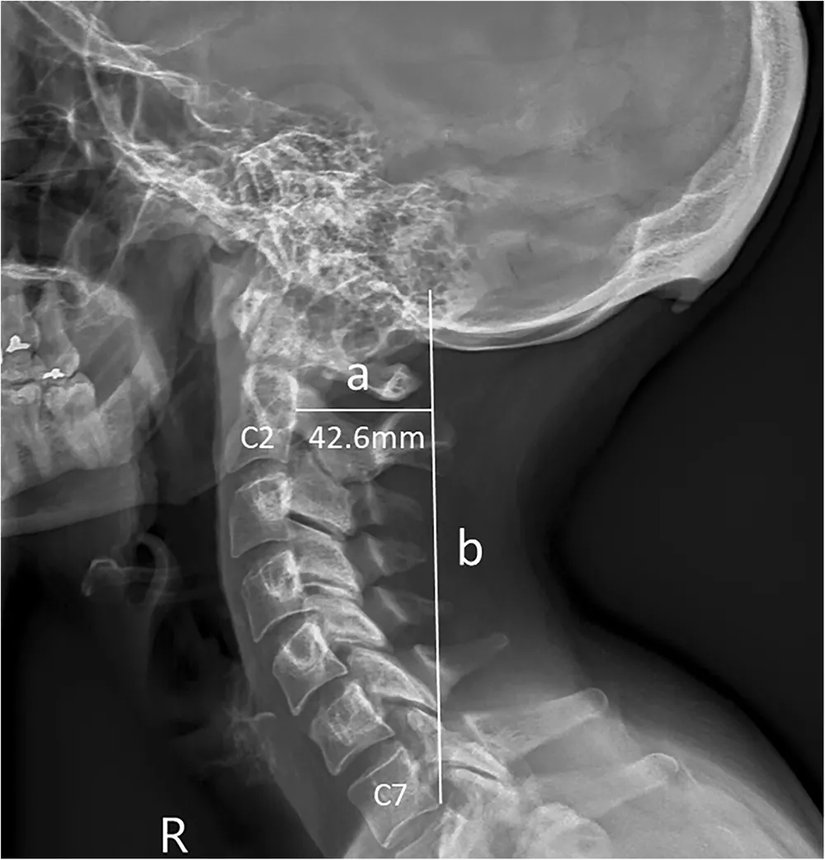

Söz konusu kemik uzantısını ortaya çıkaran veriler, 3 yıldır boyunca Avustralya'nın Queensland bölgesinde çekilen X-ışını taramalarından geliyor. Bu taramalarda, söz konusu çıkıntıların da bulunduğu bölgenin fotoğrafları çekildi. Normalde bu kemik uzantıları çok şaşırtıcı değil ve yaşlılarda görülüyor; çünkü yıllar yılı hayatta kalıp, boyun kaslarına yük bindirince, bu kemikler de ilerleyen yaşlarda gelişebiliyor. Ancak şaşırtıcı olan, genç yetişkinlerde de bu kemiklerin gözükmeye başlamış olması. Hem de kimi zaman bu genç yetişkinlerde yaşlılardan bile daha uzun kemikler görülüyor!

Aynı araştırmacılar, 2016 yılında Journal of Anatomy dergisinde yayınladıkları makalede, 18-30 yaş arası 218 kişiye ait X-ışını taraması fotoğrafını analiz ederek bu kemik büyümesinin genç yetişkinlerin %41'inde görüldüğünü tespit etmişlerdi. Bu kemikler, erkeklerde kadınlara göre daha belirgindi.

Genişlemiş dış oksipital çıkıklık (İng: external occipital protuberance) adı verilen bu durum eskiden gençlerde çok nadiren görülmekteydi. Ancak 2018 yılında Clinical Biomechanics dergisinde yayımlanan bir çalışma, bunun gençlerde daha sık görülmeye başlandığını ve sebebinin genetik veya enflamasyon gibi faktörler olmadığını; daha ziyade mekanik yük binmesi sonucu olduğunu gösterdi.

İşte bundan yola çıkan araştırmacılar, nihayetinde 18-86 yaş arası insanlara ait 1200 X-ışını taramasını inceleyerek, bu kemiklerin popülasyonun %33'ünde bulunduğunu ve şaşırtıcı bir şekilde artık yaş ilerledikçe bu kemiklerin kısaldığını gösterdiler! Bu keşif, yerleşik bilimsel bilgilerimizle fazlasıyla zıt. Çünkü normalde bu çıkıntılı kemiklerin ilerleyen yaşlarda daha da uzadığı düşünülmekteydi! Shahar şöyle diyor: